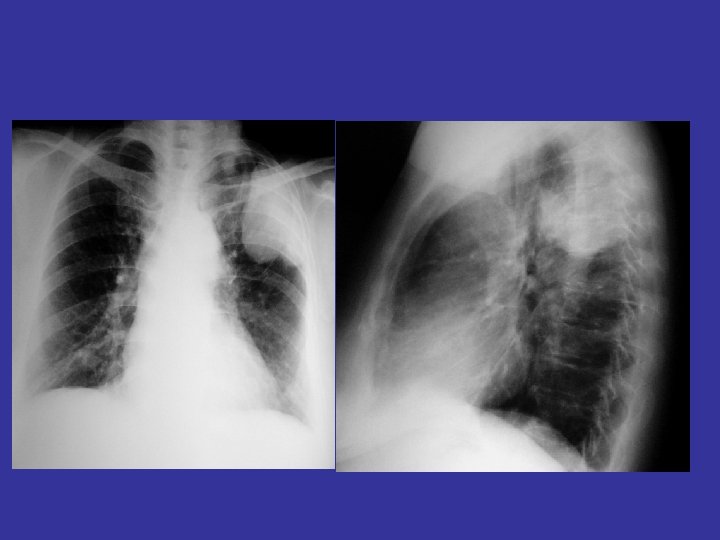

lateral view ? ! can detect otherwise hidden masses

The lateral chest film our best friend • Find abnormalities on the frontal film

The lateral chest film our best friend • Find abnormalities on the frontal film • Confirm abnormalities suspected from frontal film • Don’t be afraid to look at it